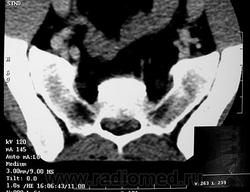

ГМ. СМ. Гигантоклеточная опухоль. +

Гигантоклеточная опухоль рояснично-крестцовой области.